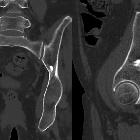

Osteom in den Beckenknochen

Osteom Radiopaedia • CC-by-nc-sa 3.0 • de